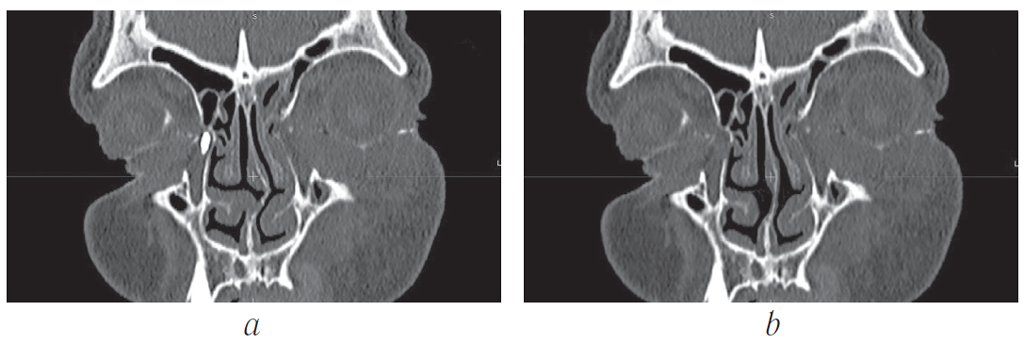

All the patients underwent multislice spiral computed tomography (MSCT) of the middle zone of the face with a contrast of the tear-removing system. The contrast was made using a standard method with a water-soluble radiopaque substance “Omnipak” 320 mg I/ml. MSCT was made on the multislice spiral computer tomographs Phillips Brilliance 64 (Phillips, USA) and TOSHIBA AQULION PRIME in a spiral scanning mode with a slice thickness of 0.6–0.9 mm. A positioning was carried out by laser marks with the patients lying on their back with a standard headrest, and the view is directed straight. The anatomical area of the scan was determined by the tomogram (surview), during the initial examination with the capture of the entire skull. The slices were parallel to the solid sky. According to the results of the MSCT dacriocystography, the degree of patency of the lacrimal pathways, the location of the tear outflow disorder and pathological changes in the lacrimal sac, possible deformity of the facial bones, and changes in bone structures and soft tissues were evaluated [8, 9] (Fig. 4, 5).

Fig. 4. MSCT – dacryocystorhinography. Ectasia of the lacrimal sac. Deviation of the nasal septum

Fig. 5. Patient G., 64 years old. Multispiral dacryocystorhinography: a – on the right, the contrast agent fills the lacrimal sac. Deviation of the nasal septum. Difficult nasal breathing; b – 6 months after. After endoscopic endonasal dacryocystorhinostomy with correction of the nasal septum and thermal destruction of the inferior turbinate. On the right, a bone window is visualized on the lateral wall in the area of the lacrimal sac projection. The tear passes freely. Free nasal breathing